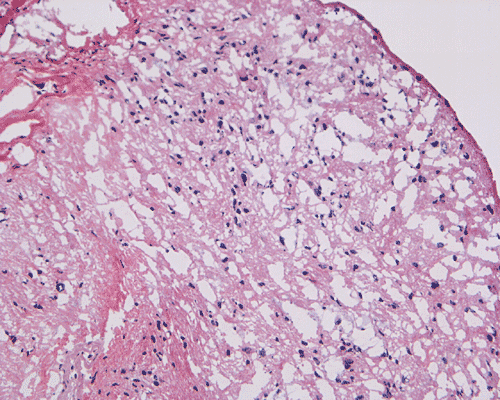

Panel A is T1-weighted post contrast MR image, Panel B is a SPGR T1-weighted post contrast MR image and Panel C is FSE T2-weighted image. Panel D and E are taken from cytologic preparation from intraoperative consultation. Panel F to H are taken from frozen sections. Panel I to L are taken from paraffin section.

Pathology of the case: A small specimen was obtained by endoscopic biopsy. The specimen cannot be smear out after being squashed and remain as several, large, stellate-shaped cohesive clumps (Panel D). The edges of these clumps are relatively thin and allows better observations. The nuclei do not appear to be pleomorphic. Many elongated cytoplasmic processes can be seen (Panel E) and are suggest a glial nature of these cells. The lesion gives a spongy appearance on low-magnification (Panel F). On medium-magnification, there are some clustering of nuclei (Panel G). On high-magnification, the nuclei appear hyperchromatic and pointy but no substantial pleomorphism, prominent nucleoli, or mitotic figure. Some bluish, mucoid material is identified in some microcysts (Ú in Panel H).

There is no endothelial proliferation or necrosis. An  intraoperative diagnosis of glial neoplasm was made. The lesion was entirely resected. On paraffin section, the lesion has a hypocellular background decorated by many small microcysts, often in clusters, that contain mucoid material and small cluster of nuclei that resemble bundles of flowers (Panel I and J).  The nuclei are bland. There was no mitosis, endothelial proliferation or necrosis (Panel K and L).